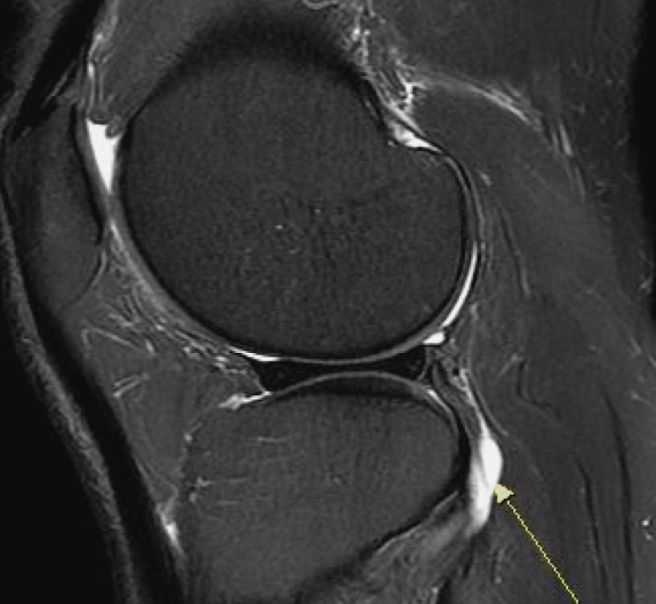

평소 하루 2만보 가까이 걷기를 즐겨하며 지내던 중 갯바위 바다낚시에서 불편한 자세로 종일 서 있었는데 그.후에 양 무릎이 불편하기 시작했습니다. 엑스레이 초음파에선 이상 없었고 오른쪽 MRI 찍어보니 연골판 바깥쪽 붓기와 더불어 근위 경골 관절에 물참/슬개건에 미세한 음영변화/내측.거위발건 염증/연골 찢어짐 없음 으로 판정 받았습니다..쪼그려 앉기 통증. 계단 무리하면 한번씩 통증. 의자에 앉아 있을때 불편감등 연골연화증 증세가 있습니다. 연화증이 맏을까요? 맞다면 어떤 치료를 해야할까요..쉬면서 근육 키우는 수밖에 없나요

• 1번 째 사진

영상소견과 증상을 종합적으로 고려했을 때 연화증이 의심되는 상태가 맞습니다.